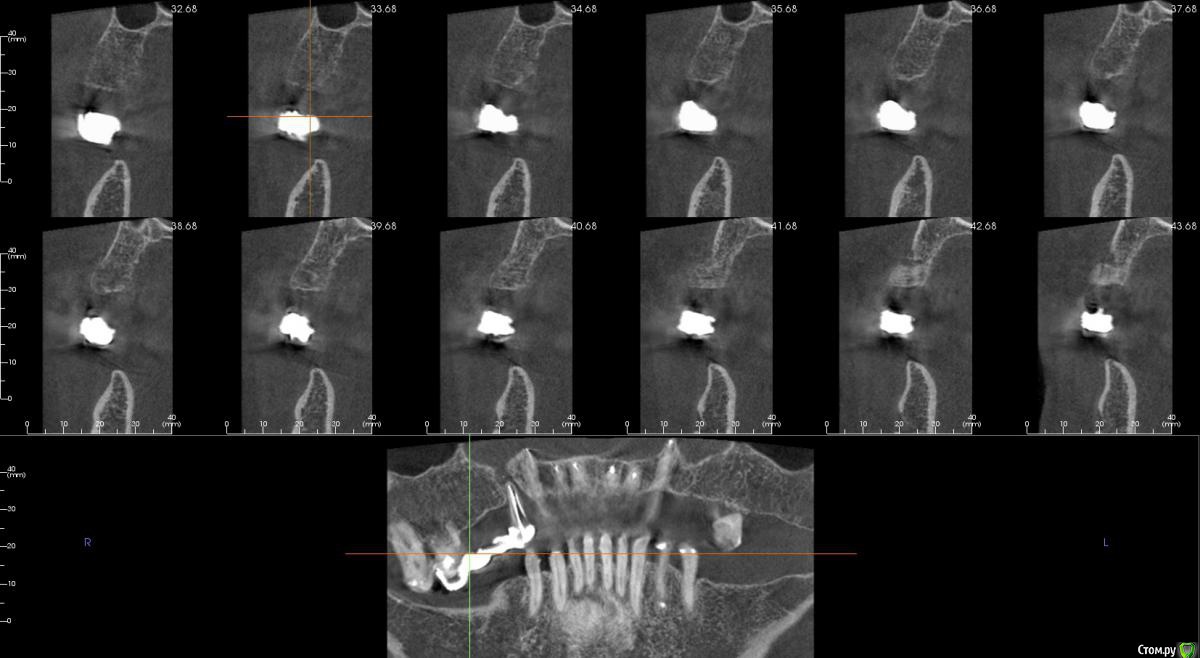

kamranchick Опубликовано 30 июня, 2016 Поделиться Опубликовано 30 июня, 2016 Господа, поставил имплантаты без сверления, прошел только 1 фрезой 2.0какие перспективы? и когда можно начинать протезирования? Ссылка на комментарий

kamranchick Опубликовано 30 июня, 2016 Автор Поделиться Опубликовано 30 июня, 2016 Я бы полгода подождал. Были такие же случаи, в основном пациенты в возрасте, либо адентия двоек.почему спрашиваю, торка я на 1 6 не получил, заглушка прокручивалась вместе с имликом, решил и заглубить Ссылка на комментарий

kamranchick Опубликовано 1 июля, 2016 Автор Поделиться Опубликовано 1 июля, 2016 Толщина большая ,можно было остеокомпрессорами сконденсировать кость.я конденсировал мисом, толку нету, торк в 16 не получил Ссылка на комментарий